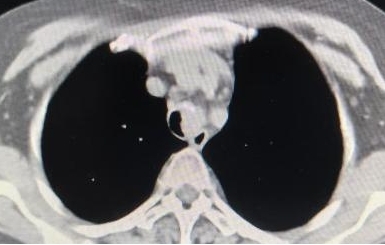

术前

原发性气管肿瘤是指原发于第一气管环以下至隆突以上范围内的气管肿瘤、多起源于气管后壁的膜部与软骨交界处的黏膜上皮和腺体,为呼吸系统的少见病症。成人主气管平均长度12cm,一般手术切除一期吻合最大长度不超过5cm。该患者主气管长度仅10cm,术中切除气管长度4cm,上、下切缘各2mm,切除总长度达4.4cm,近主气管一半长度,术中配合双侧肺门松解最大限度保证气管切除长度、最大限度降低气管吻合口张力,术后未进行下颌前胸减张缝合,大大提高患者术后舒适感加速患者康复。